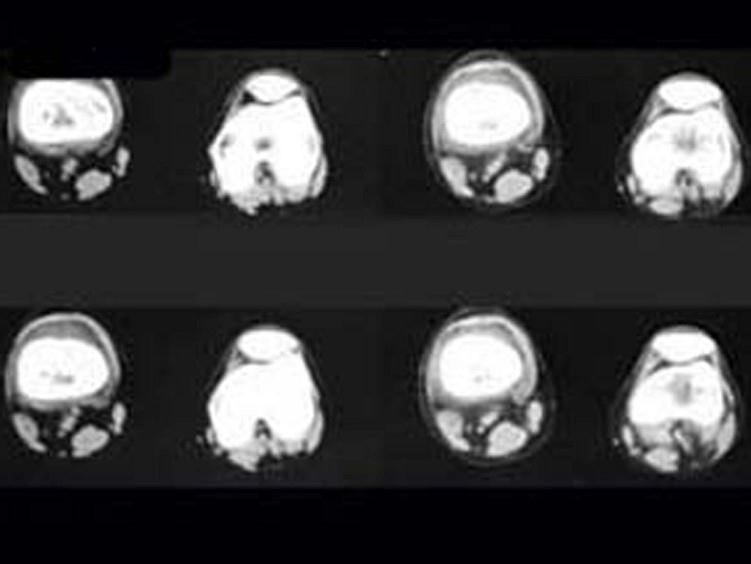

问题 男,36岁,左大腿以局部疼痛就诊,夜间疼痛加剧,请结合所提供的图像,选择最佳选项 ( )

选项 A、纤维性骨皮质缺损 B、非骨化性骨纤维瘤 C、骨样骨瘤 D、骨纤维异常增殖症 E、良性骨母细胞瘤

答案 C